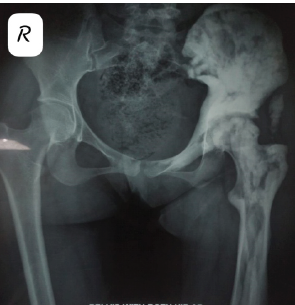

Bilateral Total Hip Arthroplasties Secondary to Renal Osteodystrophy in a Patient with a Rare Cromer Antibody: A Case Report

Anisha Tyagi , Caldon Jayson Esdaille , Ajith Kumar Kannan , Jennifer Joseph , James Lee Jr , Rahul Mittal

………………………………p.244-249